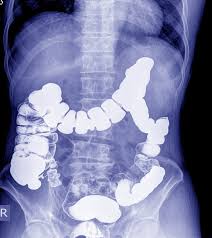

Signs Of Bowel Cancer Au : Dkzuf Ccyg6mqm - Bowel cancer occurs when abnormal cells in the wall of the large intestine grow in an uncontrolled way.. These symptoms can occur after you eat and can be so uncomfortable that they cause a reduction in food intake (and eventual weight loss). Each week 80 australians die from bowel cancer, claiming the lives of approximately 5,375 australians every year. A feeling of fullness or bloating in the abdomen (belly) or a strange sensation in the rectum, often during a bowel movement. Bowel cancer is the third most common cancer affecting people in australia. Around 8,400 men are diagnosed with bowel cancer each year, including 753 (9%) under age 50.

Colon cancer can be diagnosed at any age, but a majority of people with colon cancer are older than 50. Bowel cancer grows from the inner lining of the bowel (mucosa). How common is bowel cancer? Bowel cancer occurs when abnormal cells in the wall of the large intestine grow in an uncontrolled way. Bowel cancer is the third deadliest cancer in men, claiming more than 2,400 lives each year, including 133 (5.4%) under age 50.

Don T Put It Off Get Checked For Bowel Cancer Today Peninsula Health from www.peninsulahealth.org.au How common is bowel cancer? The rates of colon cancer in people younger than 50 have been increasing, but doctors aren't sure why. Bleeding from your bottom or blood in your bowel movements, even if only occasional a change in bowel habits for longer than two weeks, such as: It usually develops from small growths on the bowel wall called polyps. Bowel cancer occurs when abnormal cells in the wall of the large intestine grow in an uncontrolled way. Abdominal pain, bloating, and nausea are also potential signs of colon cancer in females. About 1,400 people diagnosed are under the age of 40. Bowel cancer is the third most common cancer affecting people in australia.

Sitting Down At Work Can Increase Your Risk Of Bowel Cancer By 44 Direct Endoscopy from www.directendoscopy.com.au The early signs and symptoms of bowel cancer can be easy to miss, but they may include: Bowel cancer occurs when abnormal cells in the wall of the large intestine grow in an uncontrolled way. In particular, a greater frequency of bowel movements and looser stool may be a sign of colon cancer. It is estimated that about 15,500 people are diagnosed with bowel cancer every year. However, you should see your doctor if you notice: A feeling that the bowel hasn't emptied completely. Around 8,400 men are diagnosed with bowel cancer each year, including 753 (9%) under age 50. Bowel cancer is cancer in any part of the large bowel (colon or rectum).